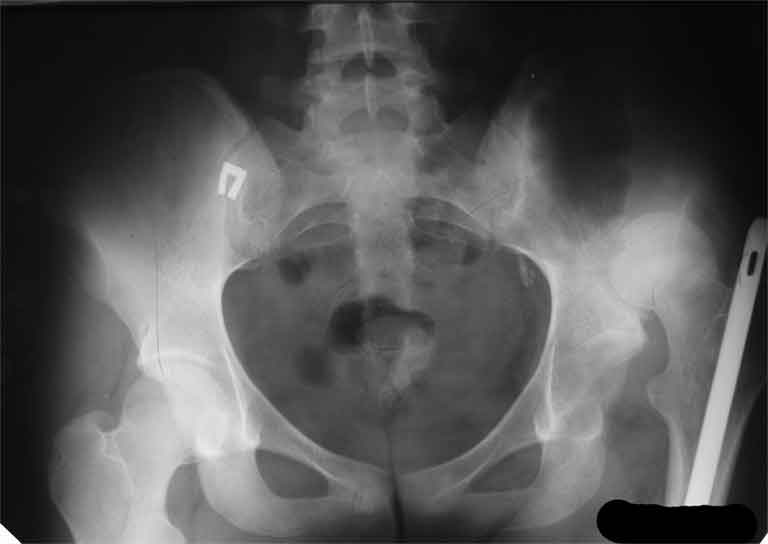

Насчет 8 см согласен с А.Н. Челноковым, это наверное ортопедическое за счет приводящей, сгибательной контрактуры и, возможно, колена. на ликвидацию укорочения у нас обычно уходит около 2-х нед. снимки в приложении, возможно не очень показательные, но других с ходу не нашел, завтра еще поищу.

Еще пара фото, ситуация несколько иная, задачи те же, открытое вправление застарелого вывиха в 2002, молодой возраст. Сейчас госпитализирована для эндопротезирования.

А за счет чего такое укорочение? По снимку не видно соответствующего дефекта. Ну плюс приводящая контрактура - но все равно как-то уж больно много. Может, сделать снимки и таза обзорный с обоими проксимальными отделами бедра, и коенный суставов с приложенной линейкой какой?

Судя по снимку, максимум истинное укорочение около 4 см, что может быть коррегировано интраоперационно. Вопрос в другом: куда ставить ацетабулярный компонент в истинную или во вновь сформированную ( впадина диспластичная).

Невозможно не согласиться с Анатолием, чтобы заниматься адекватным планированием как минимум прямая проекция таза должна быть сделана, как

максимум для оценки состояния мышц( насколько реально возможно низвести бедро) прямая проекция таза с тракцией за больную ногу.

По рентгенограммам укорочение не более 4 см, остальное возможно за счет контрактуры. Опыта с низведением аппаратом Илизарова нет, но мы одномоментно такие укорочения корригировали вполне успешно (в год 5-10 именно таких и проходит). Лишние этапы пожалуй только будут способствовать инфекции. Доступ чаше применяем передне-наружный, а вот протез наверное поставили бы здесь на цементе - остеопороз выражен.

The X ray that you provided does not show 8 cm of shortening. Perhaps you could send one showing the whole pelvis and proximal femurs.

I agree with Dr Eid's comments. The origin of the 8 cm leg length difference is a puzzle. Is this a clinical measurement? In that case contracture of the joint might affect the measurement. Can we see an AP pelvis to include both hip joints (including a calibration object with a known length) so that the difference in leg lengths that can be ascribed to the hip deformity and bony reabsorption can be measured. This sort of xray will help with templating for the TJR also. I would be very tempted to do a one stage procedure and accept some shortening. Shoe lifts should take care of a 3-4 cm difference.

До травмы проблем с ногой не было. Укорочения, болей и т.п. не отмечал. Сегодня перемерял укорочение - меньше 7 см намерять не

По уровню малых вертелов (с учетом рентгеновского увеличения) получается 5 см. Клинически ногу низвести путем тракции невозможно. Из движений - сгибание до 40*, остальные движения "символические".

Ортопедическое укорочение пострадавшей ноги может быть и 7, и 10 см. за счет контрактур в тазобедренном суставе, а вот истинное укорочение, судя по представленным рентгенограммам, вряд ли больше 4 см.